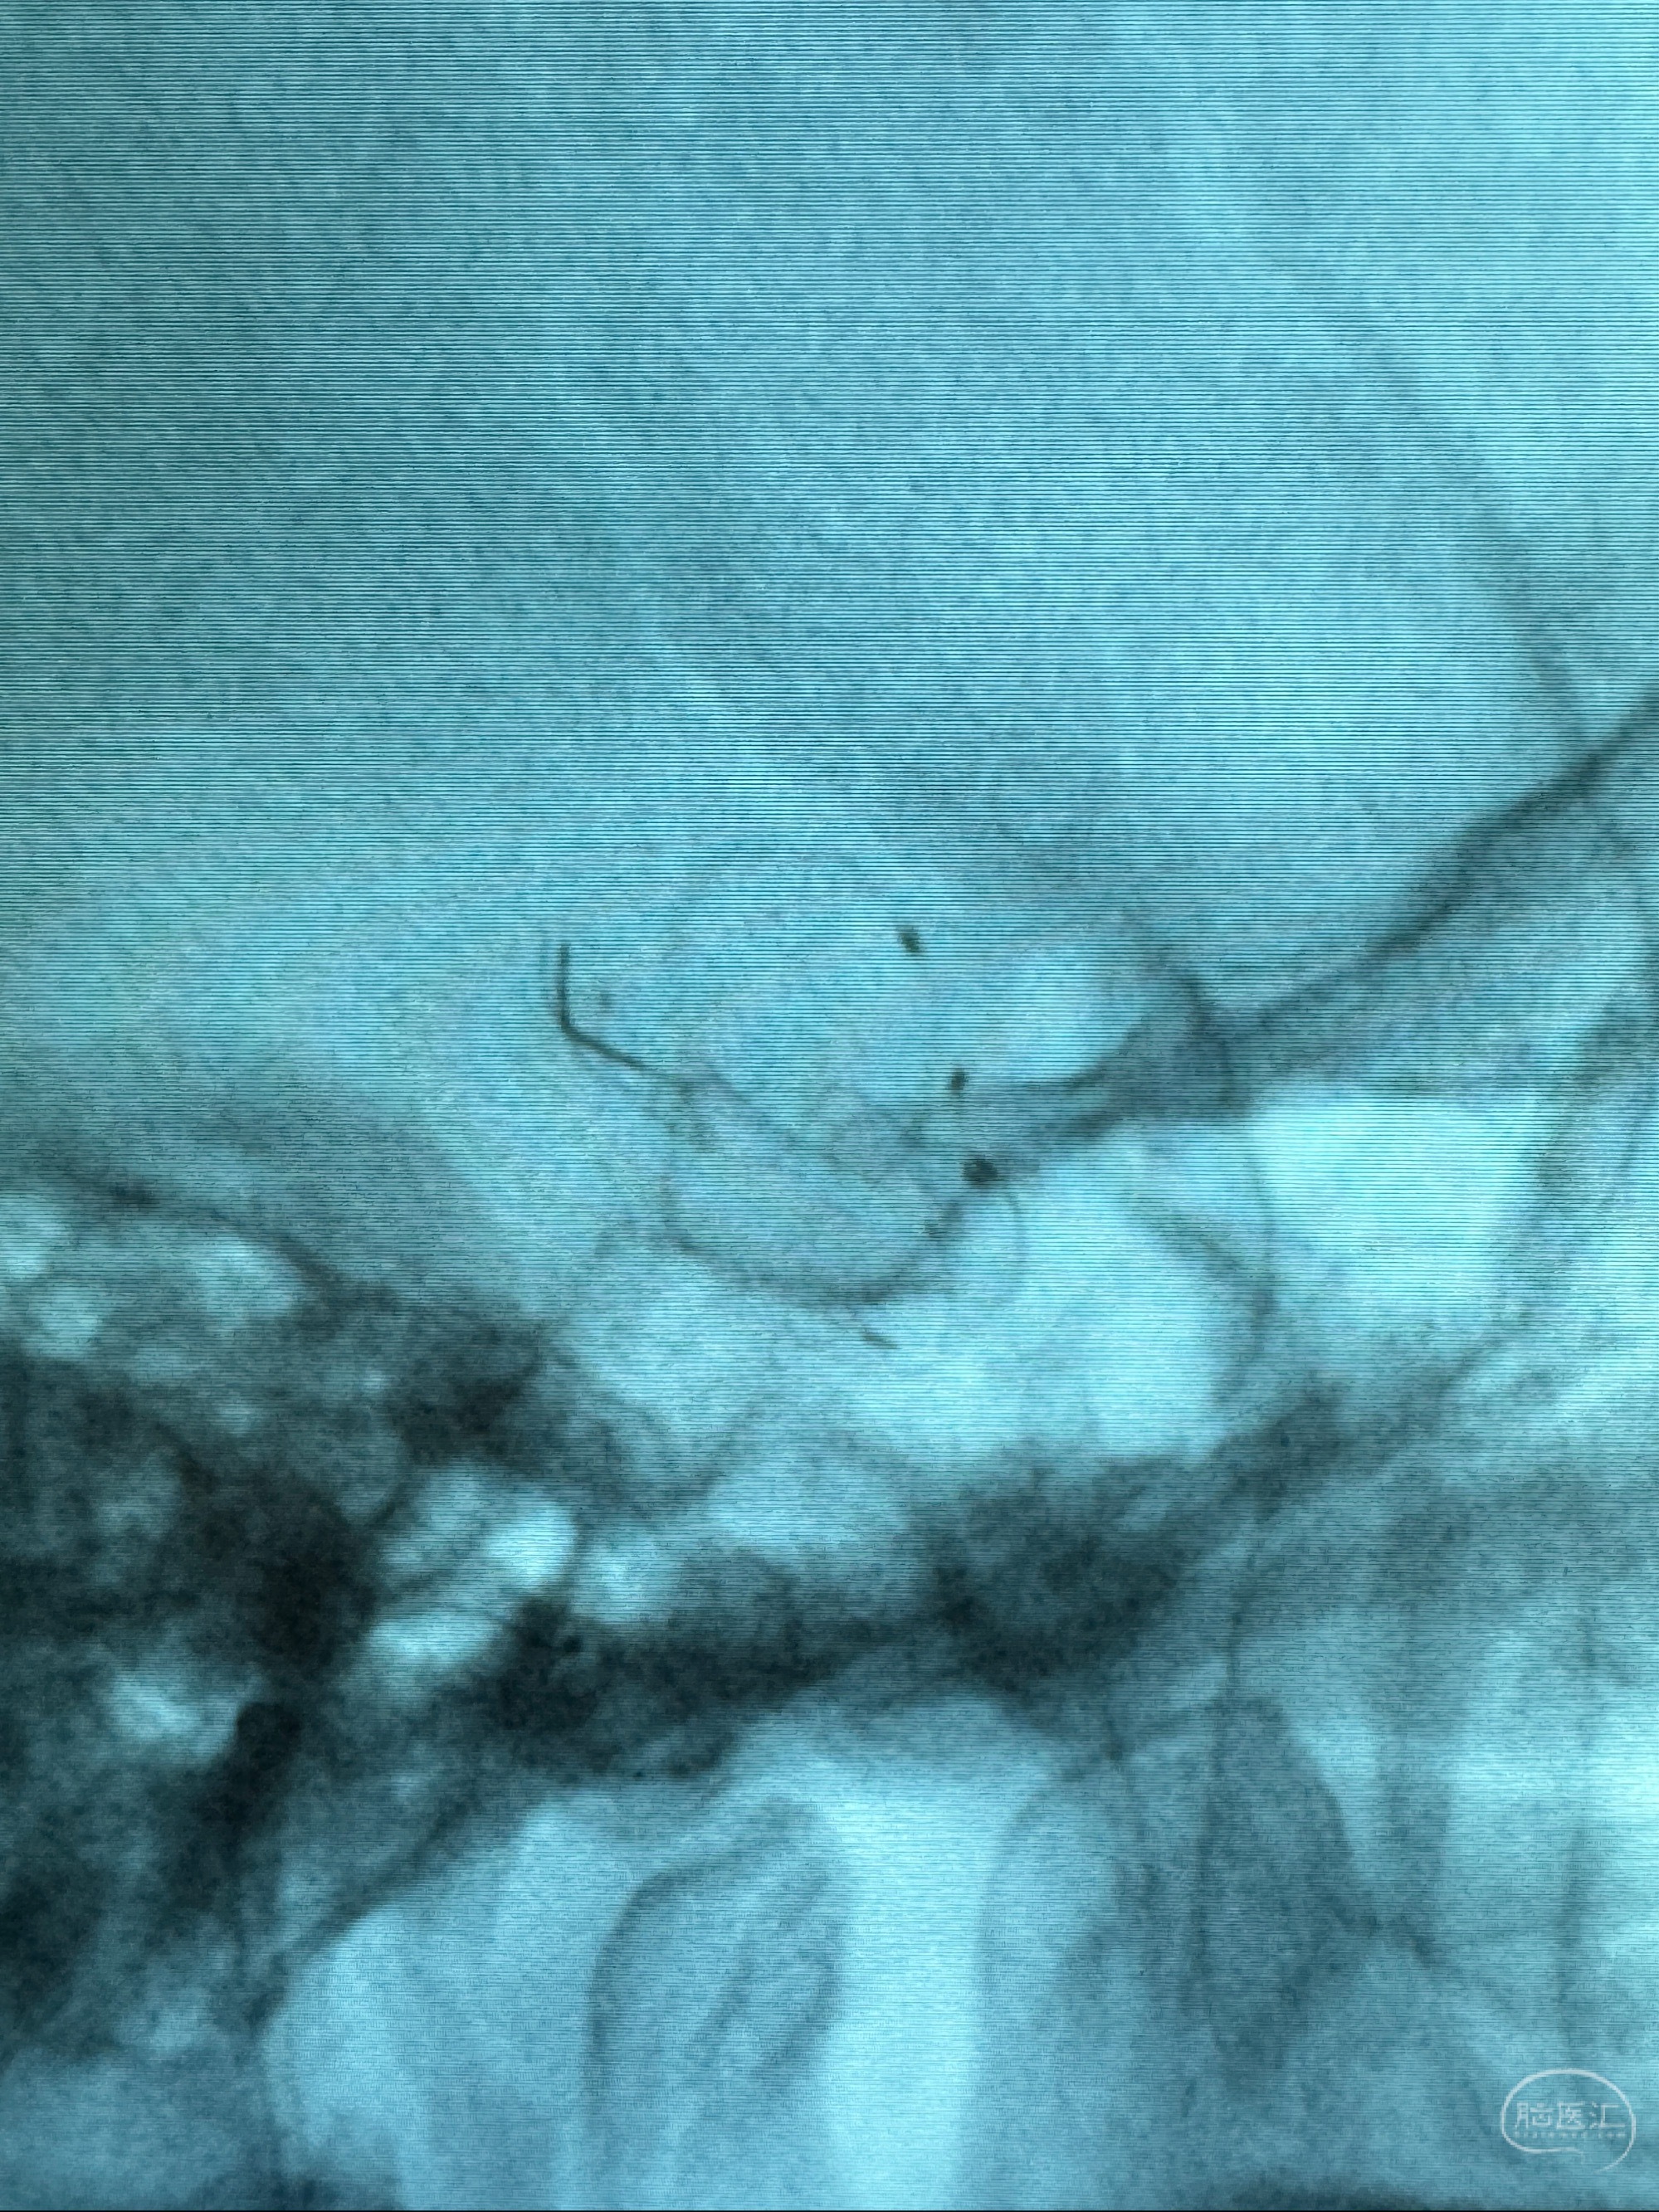

透视可见红圈部分为支架导管的头端

手推冒烟显示支架位置及展开情况,箭头为支架导管的位置

尝试回收支架失败,只能考虑释放支架了

逐帧图像展示歪着脖子释放支架,旁边吩咐助手手机摄影、拍照留像(透视机不能留影像)

接下的视频为释放支架的过程及试图确认支架与血管的关系

最后再看看颅内血管是否有异常

看动脉瘤内造影剂滞留,未见明确射流,遂撤出预留的栓塞微导管,快速结束手术,经导引导管灌注替罗非班250ug。